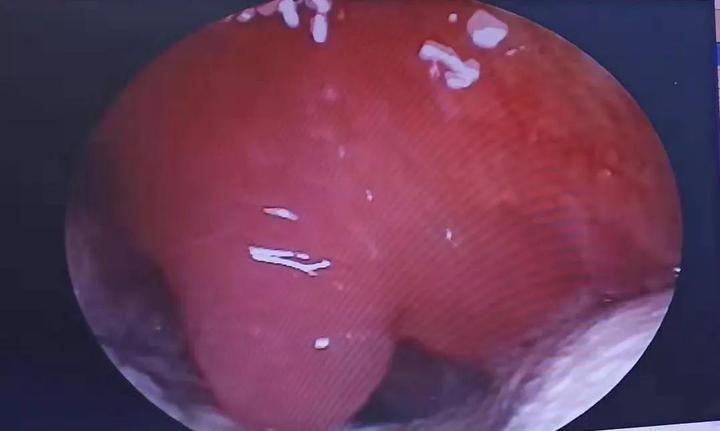

扁桃体周围脓肿切开引流术